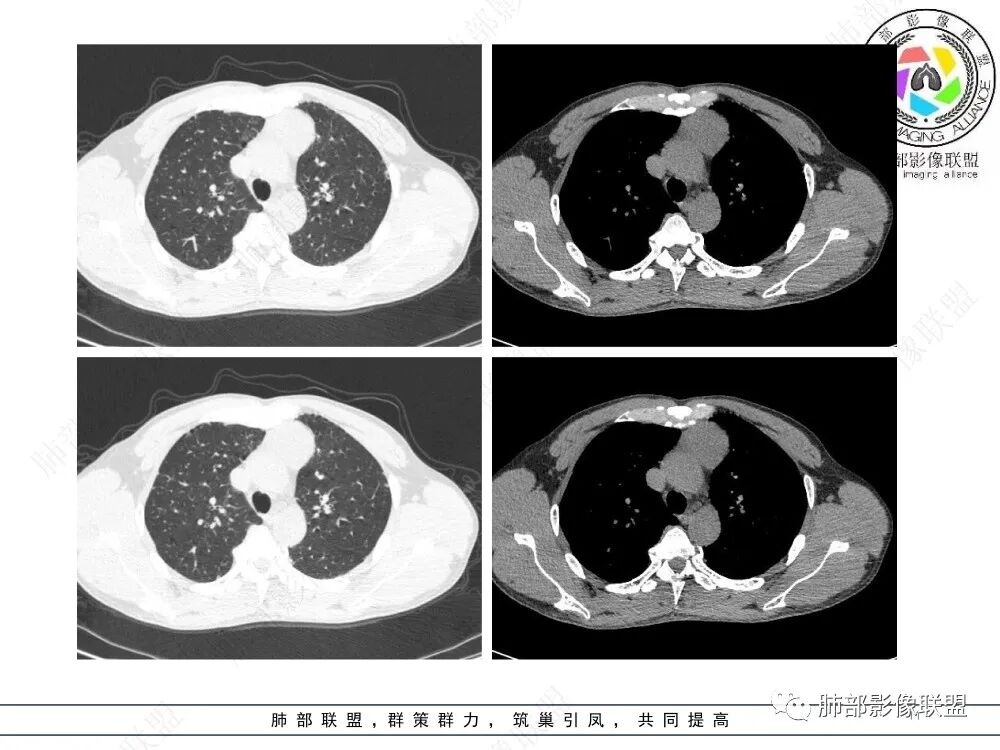

流心明智:男,47,咳嗽、咳痰1年余。胸部CT:前纵膈偏左类圆形肿块,瘤肺界面清晰光整,纵隔侧部分层面絮状影?平扫密度较均匀,增强后轻度强化,内可见宽带及线样低密度分隔。邻近左上肺受压凹陷。考虑胸腺肿瘤,AB型?胸腺Ca?鉴别淋巴瘤、N源性肿瘤、CD等。

2、影像特点:前纵隔偏左侧软组织影,密度相对均匀,未见明显包膜钙化及实质内钙化,局部边缘浅分叶,周围脂肪间隙密度增高、浑浊,未见侵犯大血管、未见纵隔内淋巴结转移、未见侵犯心包内结构、未见胸膜转移结节、未见肿块沿着纵隔胸膜蔓延,未见胸腔积液。增强后动脉期不均匀强化,未见明显纤维分隔。

3、 病 例 小 结:40岁以上,前纵隔偏侧性生长的肿块,常规考虑胸腺瘤。难点就在于胸腺瘤的分型。但是对于前纵隔占位影像诊断的关键在于区分胸腺囊肿、胸腺瘤、胸腺癌及其他恶性肿瘤。至于胸腺瘤,主要在于判断有无侵袭性。